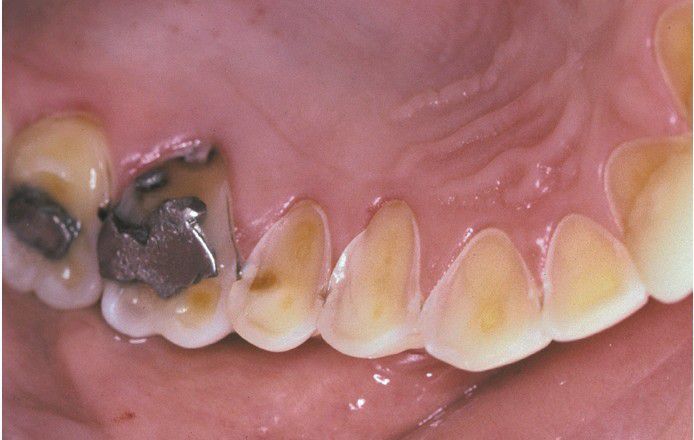

Erosion

Palatal surfaces of the maxillary dentition in which the exposed dentin exhibits a concave surface and a peripheral white line of enamel. The patient had bulimia.